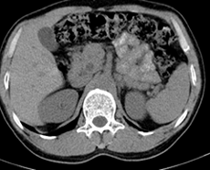

患者,男,57,常年不吃午饭,近一个月来腹部隐痛,无明显黄疸,明天进行增强扫描,图象另上传,麻烦各位帮忙一起看看讨论讨论

肝外胆管扩张,胰头增大,肠系膜上静脉似有包埋征象。

考虑:胰头占位性病变,建议增强进一步检查。

肝内外胆管扩张,胆管未端阻塞,建议mri检查

考虑肝总管或胆总管占位性病变,建议mrcp或ercp.

胰头增大,胆总管增宽,考虑胰头癌可能性大,明天看增强片有助诊断.